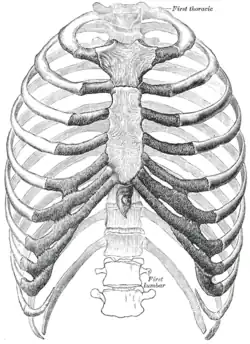

Las costillas humanas generalmente son 12 a cada lado (24 en total): 7 verdaderas o esternales (I-VII), 3 falsas o asternales (VIII-X), y 2 flotantes (XI y XII), en forma de arco con un cuerpo con dos caras, externa e interna; dos bordes, superior e inferior; y dos extremos, posterior y anterior.

Se encuentran en el tórax, constituidos por cartílago en la parte más medial de su vertiente anterior y por hueso en su vertientes lateral y posterior, que conforman la parte más visible del armazón óseo de la caja torácica, dándole un aspecto de jaula, que se articulan con cada una de las doce vértebras dorsales o torácicas en la parte posterior y con el esternón, a través del correspondiente cartílago costal, en la parte anterior.

Todas las costillas se unen en la parte posterior de las vértebras torácicas.

Las estructuras base de una costilla son:

- Cabeza: Parte interna del posterior de la costilla; se articula con la vértebra torácica correspondiente y con la vértebra que se encuentra sobre esta, a excepción de la primera y las 2 últimas, las cuales se articulan solamente con sus vértebras correspondientes. Es el extremo más voluminoso del hueso, donde existe una carilla articular hacia la columna vertebral.

- Cuello: Porción ósea angosta que se une a la cabeza.

- Cuerpo: Parte principal de la costilla. Aquí se inserta el músculo iliocostal.

- Tubérculo: El tubérculo de la costilla es una eminencia en la superficie posterior, en el cruce del cuello y el cuerpo de la costilla. Todas las costillas típicas (tercera a la novena) presentan una carilla para articular con el proceso transverso de las vértebras torácicas. En el caso de las costillas flotantes, estas carecen de esta superficie articular.

- Ángulo: La separación entre el ángulo y el tubérculo es progresivamente mayor de la segunda a la décima costillas. La porción entre el ángulo y el tubérculo es redonda, áspera e irregular, y sirve para la inserción del músculo dorsal diente vértebra torácica; falta este tubérculo en los últimos 3 pares de costillas.

- Surco: Es la concavidad entre el borde de la cara interna con el borde inferior, por donde pasa el paquete neuro-vascular intercostal (arterias, venas y nervios intercostales). También se insertan los músculos intercostales respectivos.

- Cresta: Estructura de la costilla que se encuentra ubicada en la cabeza de algunas costillas.

Todas las costillas tienen una cara externa e interna, con excepción de la primera costilla, la cual tiene una cara superior y una inferior. En el arco anterior de la primera costilla se encuentra el Tubérculo de Lisfranc, donde se inserta el músculo escaleno anterior.